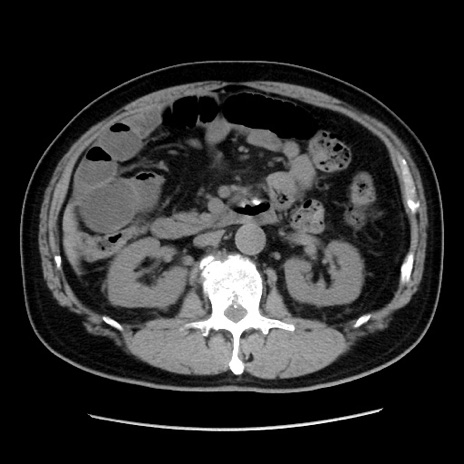

症例16(横断像)

【症例】 70歳代男性

【主訴】 腹痛、嘔吐

【現病歴】 約1ヶ月前より間欠的に腹痛と嘔吐あり、当院消化器内科を受診したところCTで多発する肝臓のLDAを指摘され、精査中であった。以降は消化器症状は安定していたが、2日前より嘔気と腹痛があり、同日より排便・排ガスが消失した。改善認めず、 本日、救急外来を受診した。

【既往歴】 大腸ポリープ切除後。

【身体所見】意識清明・会話良好、BT 36.3℃、BP 127/80mmHg、 P 80bpm、腹部:膨満あり、平坦・軟、上腹部正中および下腹部正中に圧痛あり、反跳痛なし、筋性防御なし。

【データ】WBC 7200、CRP 0.77